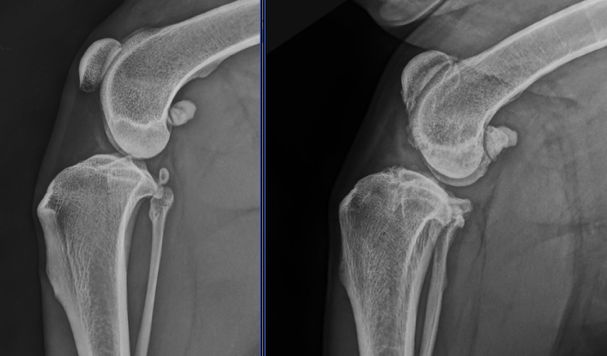

A diagnosis of OA is generally made following diagnosis of the underlying condition. In many cases we can identify the lame leg(s) and localise lameness or pain to the affected joint(s) by watching your pet walk during the consultation and a thorough orthopaedic examination. Radiographs (x-rays) can often diagnose the underlying cause of OA and allow planning of any specific treatment options (e.g. surgical management of cruciate ligament disease).

Stifle (knee) radiographs of a normal dog (left) and a dog with osteoarthritis (right). The arthritic stifle has irregular new bone formation at the margins of the joint.